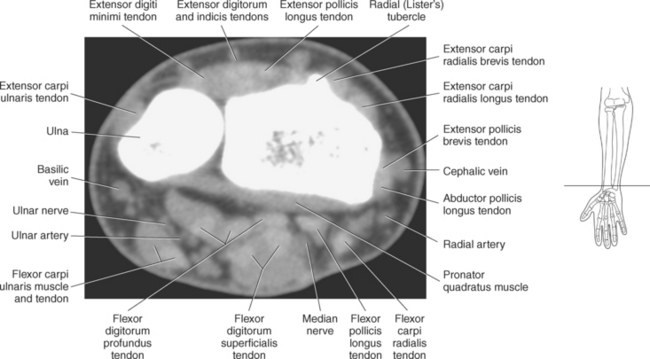

The numerous muscles of the forearm become tendinous just before the wrist joint. The many tendons located in the wrist can be divided into palmar and dorsal tendon groups (Figures 9.120, A and B and 9.127). The palmar tendon group collectively flexes the fingers and wrist. As this group courses through the carpal tunnel, the tendons appear to be arranged in two discrete rows (Figures 9.118, A and 9.119). The tendons of the dorsal tendon group, spanning the superficial surface of the wrist, are considered the extensors of the fingers and wrist (Figures 9.128 through 9.140).

The broadened distal end of the radius includes the cartilage-covered carpal articular surface, the ulnar notch, and the radial styloid process. The carpal articular surface articulates with the scaphoid and lunate bones of the wrist. The ulnar notch articulates with the ulna, and the styloid process serves as an attachment site for the extensor pollicis longus and extensor carpi radialis tendons. The dorsal surface of the radius contains several grooves that serve as passages for the extensor tendons. Along with the grooves, a prominent ridge is located on the dorsal surface termed the radial dorsal tubercle, or Lister’s tubercle, a common site for the formation of bony spurs (Figure 9.72).

Numerous ligaments provide additional stability to the wrist. The extrinsic ligaments reinforce the joint cavity surrounding the carpal region and include palmar and dorsal radial carpal ligaments, the radial and ulnar collateral ligaments, and the TFCC (Figures 9.115 through 9.117). The many articulations between the carpal bones are supported by the intercarpal ligaments or intrinsic ligaments that connect the carpal bones to each other (Figure 9.115). The configuration of the intrinsic ligaments, metacarpal ligaments, and triangular fibrocartilage complex creates five different joint compartments that can be demonstrated at arthrography: (1) compartment of the first carpometacarpal articulation, (2) common carpometacarpal compartment, (3) mediocarpal compartment, (4) intermetacarpal compartment, and (5) radiocarpal compartment (Figure 9.115). The carpal tunnel is created by the concave arrangement of the carpal bones (Figure 9.103). A thick ligamentous band called the flexor retinaculum (transverse carpal ligament) stretches across the carpal tunnel to create an enclosure for the passage of tendons and the median nerve (Figures 9.118 through 9.120). The flexor retinaculum inserts medially on the pisiform and hook of the hamate and spans the wrist to insert laterally on the scaphoid and trapezium. In addition to the carpal tunnel, another tunnel called Guyon’s canal is formed where the ulnar extension of the flexor retinaculum continues over the pisiform and hamate. This creates a potential site for compression of the ulnar nerve (Figures 9.118, top, and 9.119). The extensor retinaculum (dorsal carpal ligament), located dorsally, is much thinner. It attaches medially to the ulnar styloid process, triquetrum, and pisiform and laterally to the lateral margin of the radius (Figure 9.120, left). Along its course it forms six fibroosseous tunnels for the passage of the synovial sheaths containing the extensor tendons (Figure 9.118, bottom).